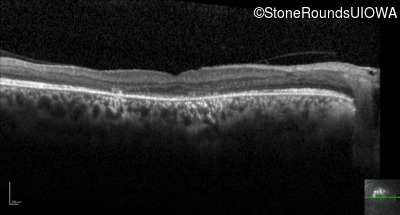

Optical Coherence Tomography - Right - Count Fingers 2'

Exemplar / OCT Stack

OCT Stack